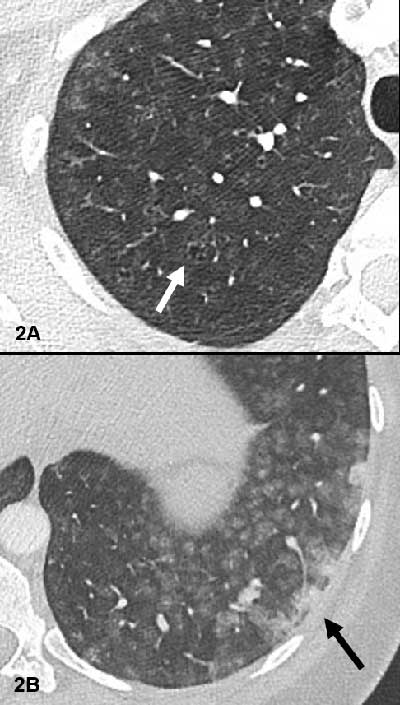

Figure 2

Small centrilobular apical emphysema (white arrow Figure 2A) and confluent condensed areas in the basal segments of the lower lobes (black arrow Figure 2B).